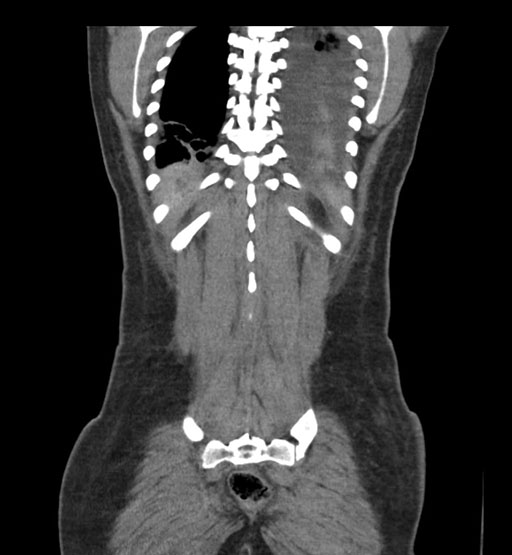

Coronal Arterial

Coronal Venous